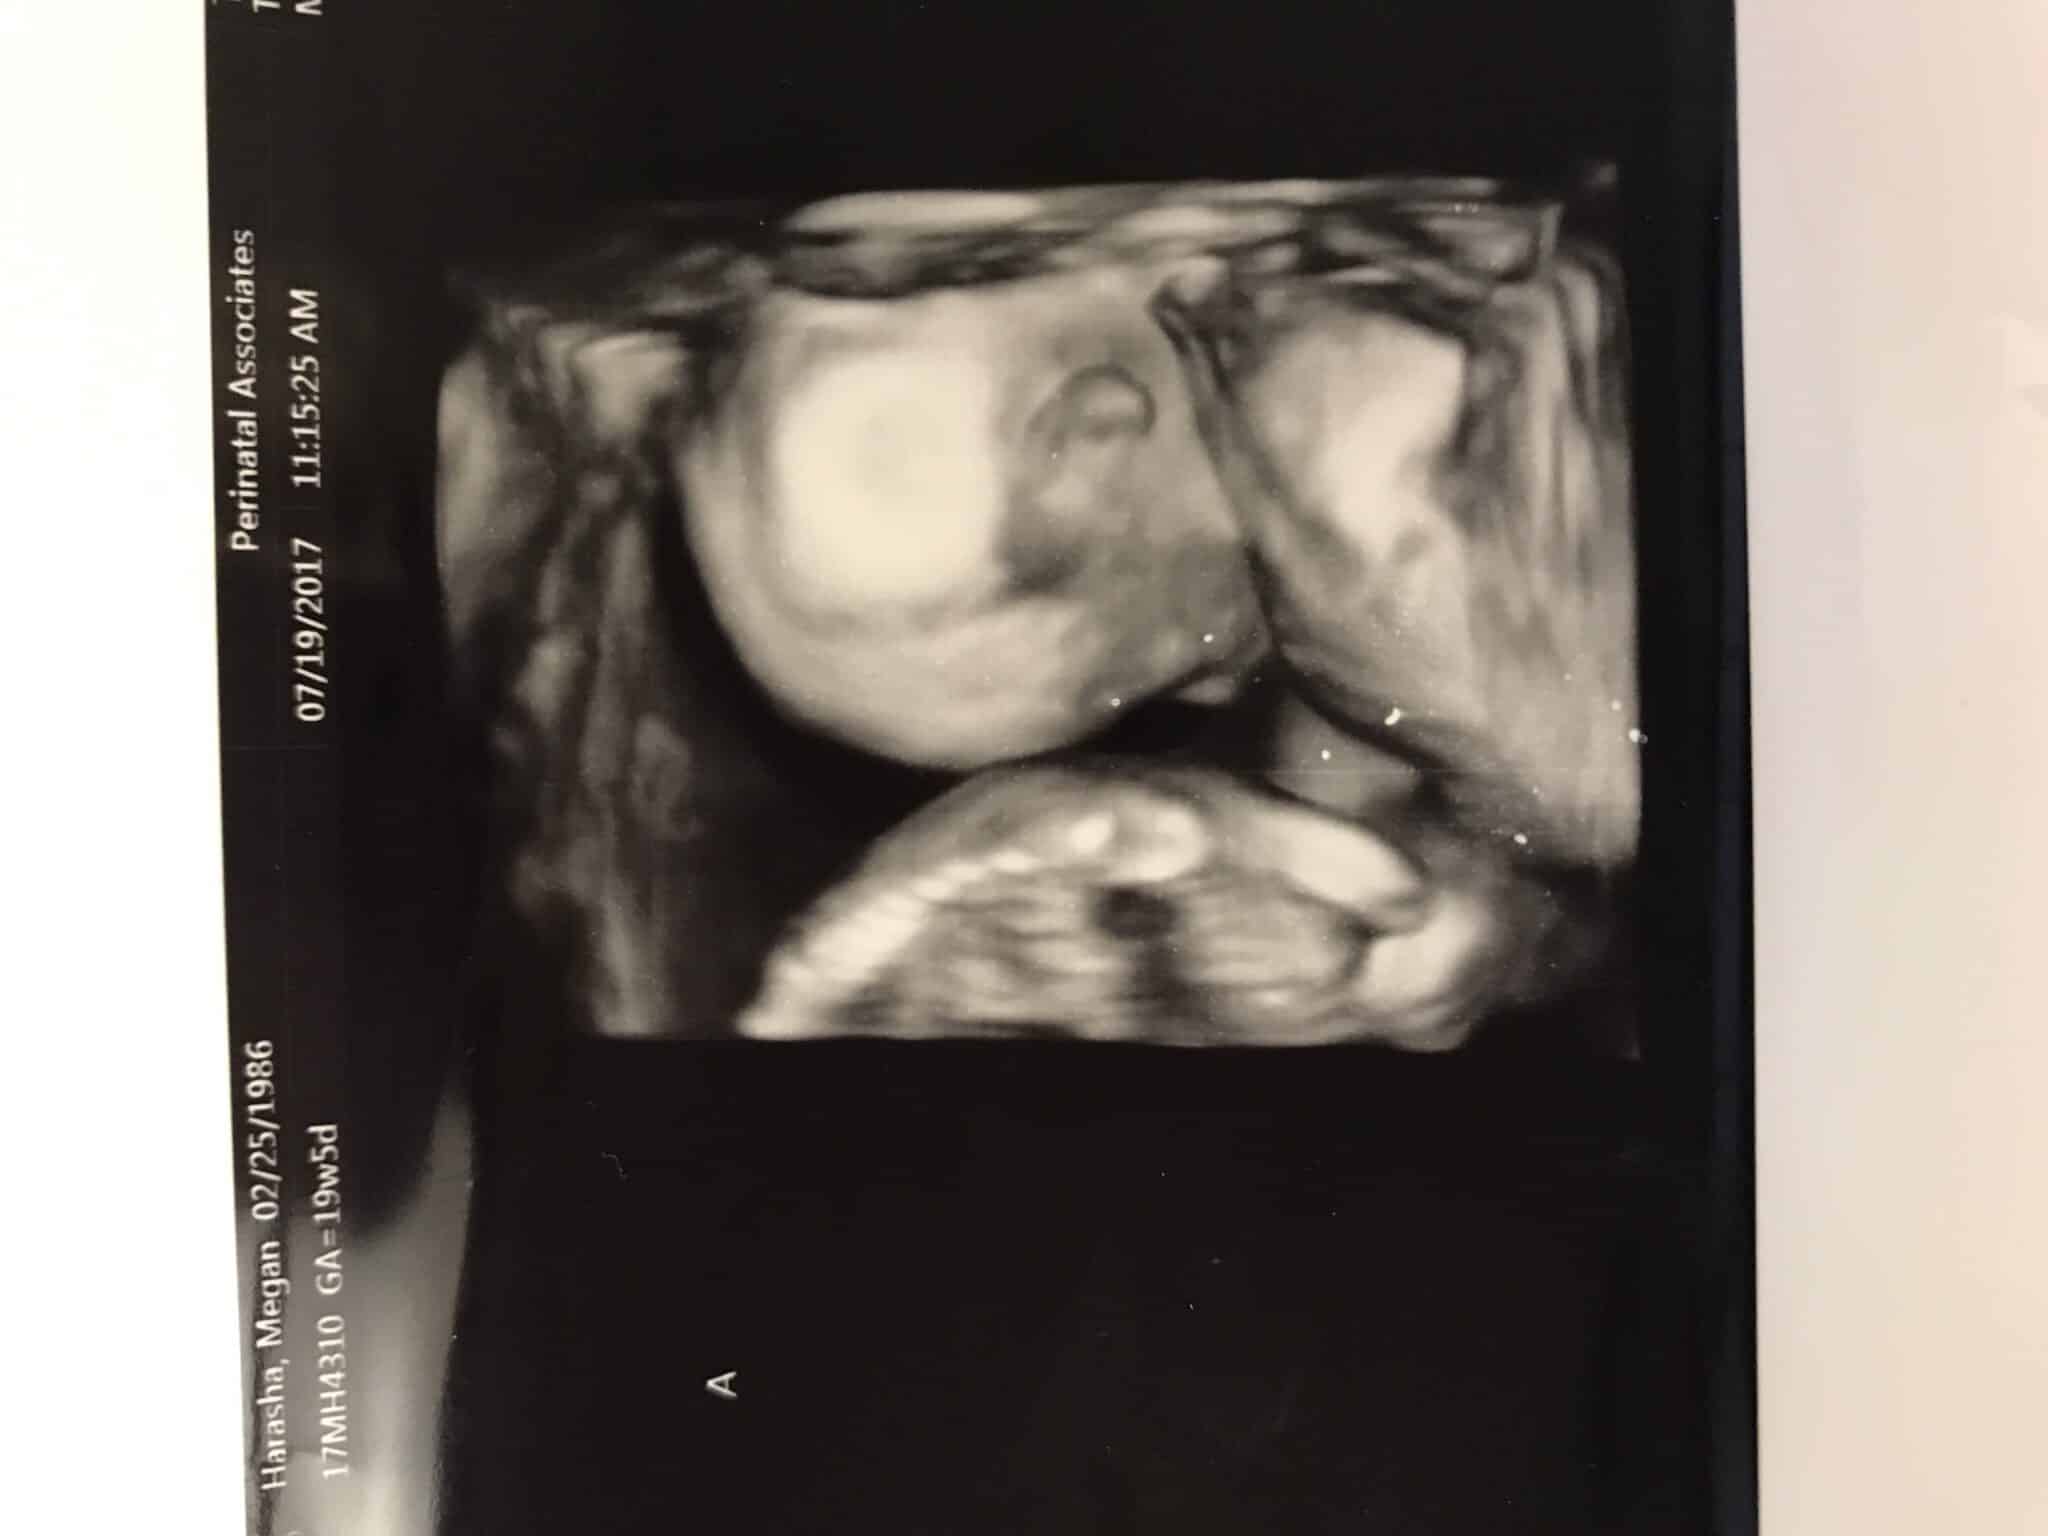

Ultrasound Photos at 19 Weeks Pregnant With Twins